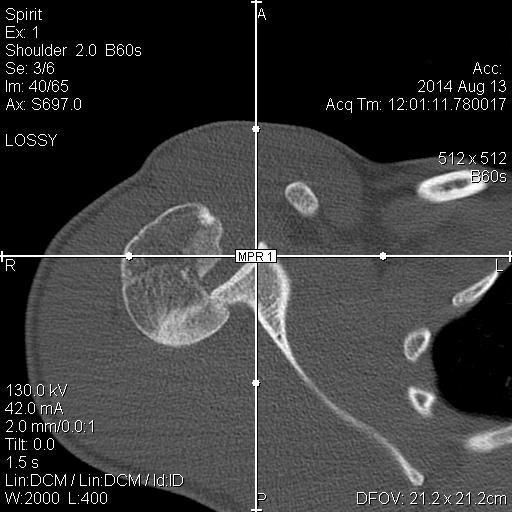

Уважаемые коллеги! 12.08.2014 поступил молодой человек 28 л. спортивного сложения (активно занимается "железом") - травма уличная - получил удар током 220В от электронасоса, затем, по всей видимости, упал на правое плечо (изначально факт падения не озвучивался). В связи с электротравмой и срывом ритма госпитализирован в ОАИТ. По стабилизации состояния начал жаловаться на интенсивные боли в правом плечевом суставе. Выполнена Р-графия правого плечевого сустава, дежурный травматолог расценил видимый костный фрагмент как отрывной перелом либо головки, либо суставного отростка лопатки; иммобилизация правой верхней конечности осуществлена бандажом. На следующий день боли в правом плечевом суставе сохранялись, осмотрен клинически - заподозрен задний вывих плеча, на повторной прямой Р-грамме ничего существенного, снимок с выведением большого бугорка не удался из-за ограничения наружной ротации. Затем выполнена КТ - диагностирован переломо-вывих правого плеча. Под общим обезболиванием вывих закрыто устранен, иммобилизация осуществлена гипсовой повязкой. Возникает вопрос: что делать дальше? Необходимость оперативного вмешательства вроде бы  очевидна, но вот его объем?  Пока планируется элевация импактированного фрагмента, остеосинтез всего этого на PHILoSе. Второе мнение - синтез фрагмента головки и малого бугорка винтами (Герберта?), фиксация большого бугорка (подшивание). Либо сочетание этих способов... Время вроде бы поджимает, хотелось бы узнать видение ситуации уважаемым сообществом.